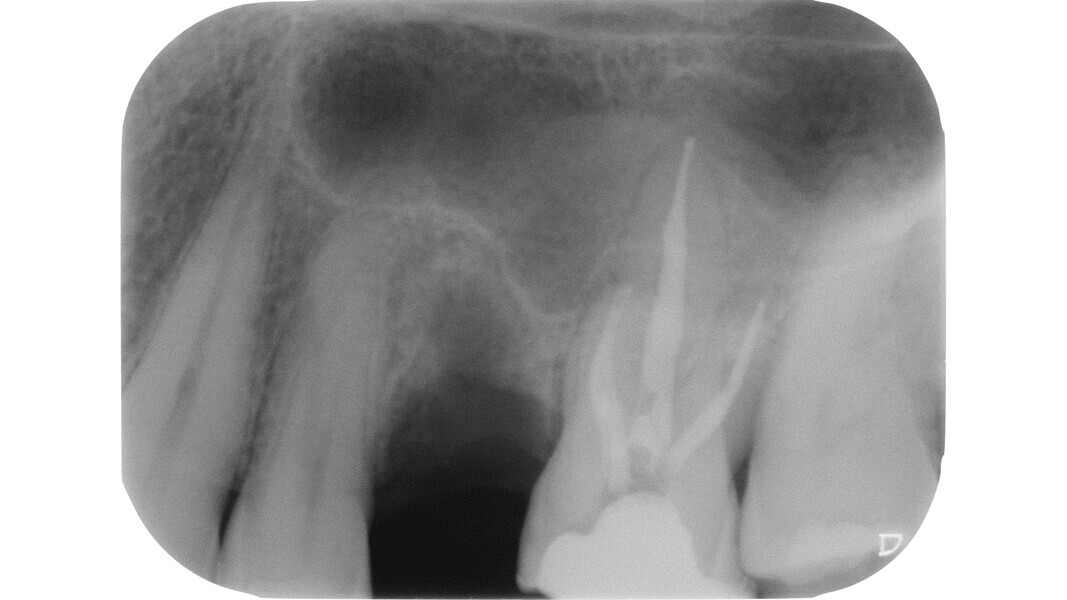

Fig. 1: Pre-op radiograph of a maxillary molar undergoing emergency treatment at another practice.

An inadequate access cavity in terms of position, depth and extension can lead to complications in the subsequent phases, making it impossible to locate the canal orifices, overstressing the mechanical nickel–titanium (NiTi) files or weakening the residual dental structure (Figs. 1–5). While, in the past, there was a tendency to emphasise the importance of a large access cavity that would allow the insertion of manual and mechanical instruments following the main axis of the canal, in recent years, the proposal of minimal access cavities defined in various ways (“ultra-conservative cavity”, “ninja cavity”, “truss access cavity”)4 has become predominant.